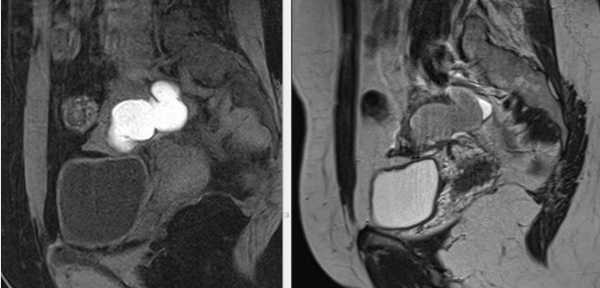

МРТ малого таза в сагиттальной плоскости. По задней стенке матки — интрамурально-субсерозная лейомиома (круг) с признаками гиалиновой дегенерации.

МРТ малого таза в сагиттальной плоскости. В структуре яичника отмечается неправильной формы эндометриоидная (“шоколадная”) киста, заполненная вязким геморрагическим содержимым.